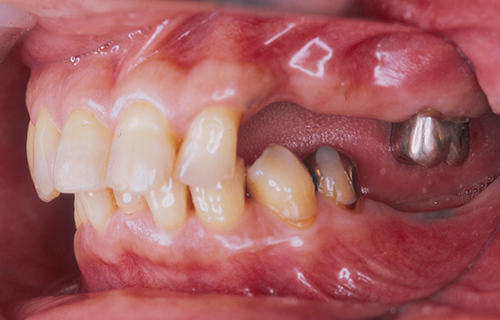

治療前(左側)

上下顎左右共に奥歯に歯がない状況で来院されました。

左側だけで、上下併せて4本のインプラント体を埋入しています。